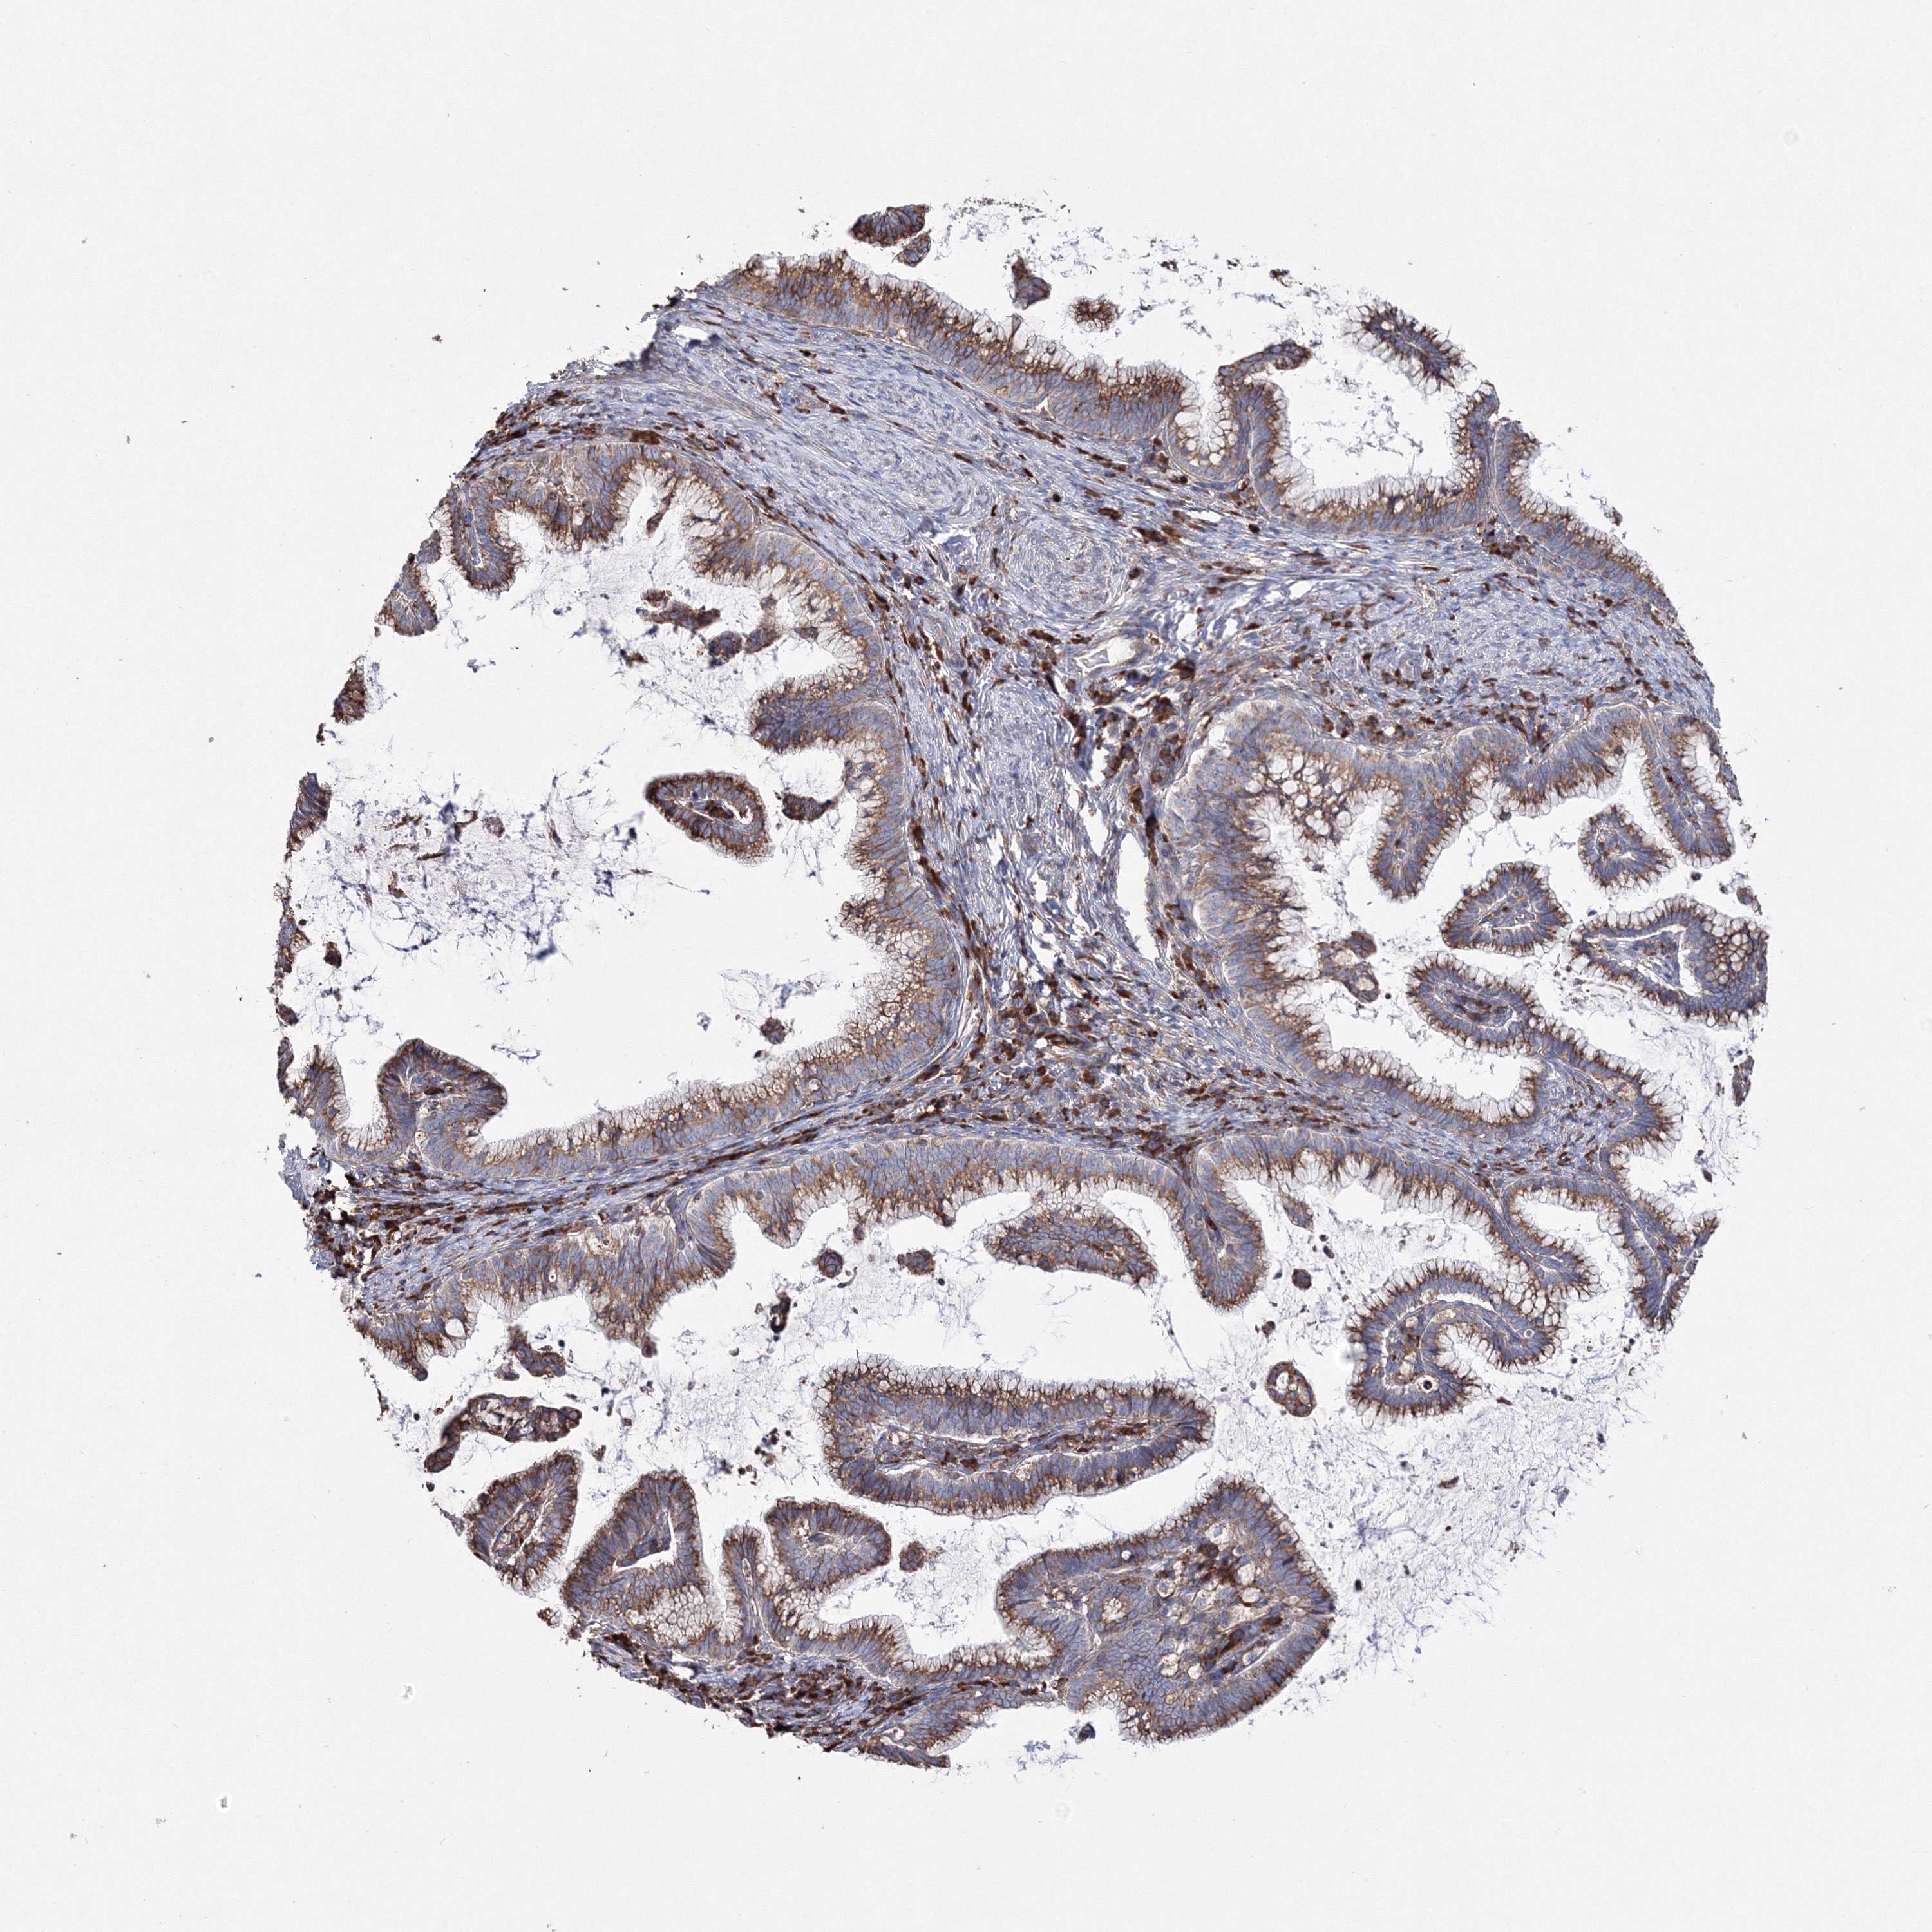

CERVICAL CANCER - Protein expressioni

A mouse-over function shows sample information and annotation data. Click on an image to view it in a full screen mode. Samples can be filtered based on level of antibody staining by selecting one or several of the following categories: high, medium, low and not detected. The assay and annotation is described here.

Note that samples used for immunohistochemistry by the Human Protein Atlas do not correspond to samples in the TCGA dataset.

Antibody stainingi

Antibody staining in the annotated cell types in the current human tissue is reported as not detected, low, medium, or high, based on conventional immunohistochemistry profiling in selected tissues. This score is based on the combination of the staining intensity and fraction of stained cells.

Each image is clickable and will lead to virtual microscopy that enables deeper exploration of all samples and also displays staining intensity scores, fraction scores and subcellular localization as well as patient and tissue information for each sample.

Antibody HPA036871

Staining

High

Medium

Low

Not detected

Intensity

Strong

Moderate

Weak

Negative

Quantity

>75%

75%-25%

<25%

None

Location

Nuclear

Cytoplasmic/membranous

Cytoplasmic/membranous,nuclear

Squamous cell carcinoma, NOS

Adenocarcinoma, NOS